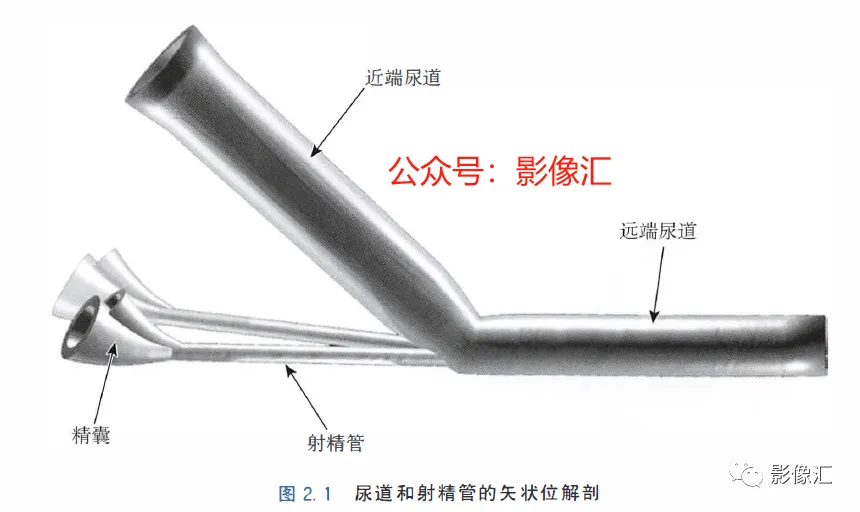

McNeal解剖模型认为前列腺根据周围不同结构环绕的关系而分为四个区域。尿道是描述整个前列腺区域解剖结构的解剖学标志。尿道由近端和远端尿道两个部分组成,每个部分约15mm长,由精阜分界。在精阜处,近端和远端尿道的走行呈35°。尿道壁由纵向走行的平滑肌纤维组成。围绕该内层的纵向肌肉层,是一层环形走行的肌层。两层平滑肌构成所谓的尿道内括约肌(IUS),其从膀胱颈延伸到尿道膜部的末端。IUS在膀胱颈的近端水平处最厚,随其向尿道膜部延伸,厚度逐渐减小。尿道膜部完整地被IUS环绕。在其前侧,前列腺内的lUS与前列腺肌性间质(AFMS)融合。两射精管走行方向与远端尿道平面平行,其开口于尿道腔内的前列腺小囊。移行带在前列腺组织中约占5%,构成两叶分别位于近端尿道两侧。其导管系统平行于尿道平面走行,止于精阜,射精管开口的近侧。移行带毗邻外周带,中央带和前列腺肌性间质,构成所谓的外科手术包膜,也就是说,确定了前列腺剜除术的外科手术平面。移行带和尿道周围腺体组织是良性前列腺增生(BPH)的发生部位。前列腺癌发生在移行带的比例为10%~20%。中央带在前列腺腺体组织中约占25%。其在前列腺底部形成金字塔形或锥形结构,在精阜水平处变窄至顶点。中央带的导管在射精管开口的两侧呈放射状走行。精囊和输精管穿入中央带形成射精管形似“精囊喙”。此区域由于缺乏前列腺包膜而成为解剖薄弱区。与射精管延续的中央带及伴行的筋膜和淋巴血管组织称为前列腺嵌入部(invaginated extraprostatic space,IES)。这是另一个解剖学上的薄弱区域,因此中央带疾病容易沿此区域播散。中央带相对发病率较低,发生在中央带的前列腺癌占5%~10%。外周带和中央带之间缺乏解剖学屏障,同时由于IES的存在,意味着前列腺尖部发生的肿瘤很容易进展到前列腺底部,并可早期造成前列腺周围间隙结构的受累。外周带约占前列腺腺体组织的70%。其包括前列腺表面的外侧、背侧和尖部,以多变的方式向腹侧延伸,与前纤维肌性间质相延续。前列腺不具有通常意义上的包膜结构,表面有一层腺样间质被称为“包膜"。前列腺“包膜”本身由纤维肌性间质构成,其在腺体周围形成一薄层结构。前列腺尖部没有这种间质层,造成一个解剖学上的蒲弱区域,称为梯形区域(trapezoidal area)。该区域腹侧以尿道膜部为界,背侧则以Denonvilliers和直肠筋膜为界,头侧以前列腺尖部(外周带)为界,尾侧则以直肠尿道肌为界。70%的前列腺癌发生在前列腺外周带。当前列腺癌起自前列腺尖部时,在早期即可通过梯形区域侵犯前列腺周围间隙。前列腺的背外侧神经血管蒂也是肿瘤易向外蔓延和侵袭的区域。AFMS约占前列腺体积的33%,是前列腺的非腺体区域,构成前列腺的前表面。在其最近端部分,其与逼尿肌和尿道内括约肌(IUS)的平滑肌纤维融合。头侧,其保持和尿道外括约肌(EUS)的关系;EUS的横纹肌纤维在该区域(前列腺尖部的前外侧)融合,构成前列腺外括约肌群。有四个“解剖薄弱“ 区域,通过这些区域,前列腺肿瘤可以生长并侵犯相邻的结构。这些区域是:精囊喙(图2. 6和图2. 17)